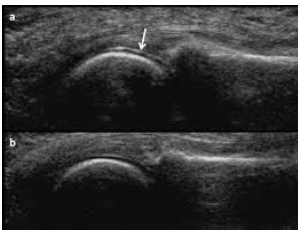

Assinale a alternativa que apresente o

método de imagem que pode auxiliar no

diagnóstico da gota e como se denomina o

sinal que é considerado específico.